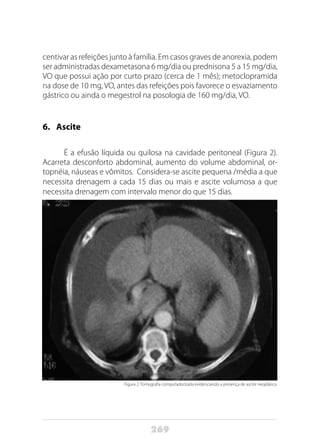

maior do PET-CT é para estadiamento do câncer pancreático. Em um es-

tudo com 46 pacientes com câncer pancreático, o estadiamento padrão